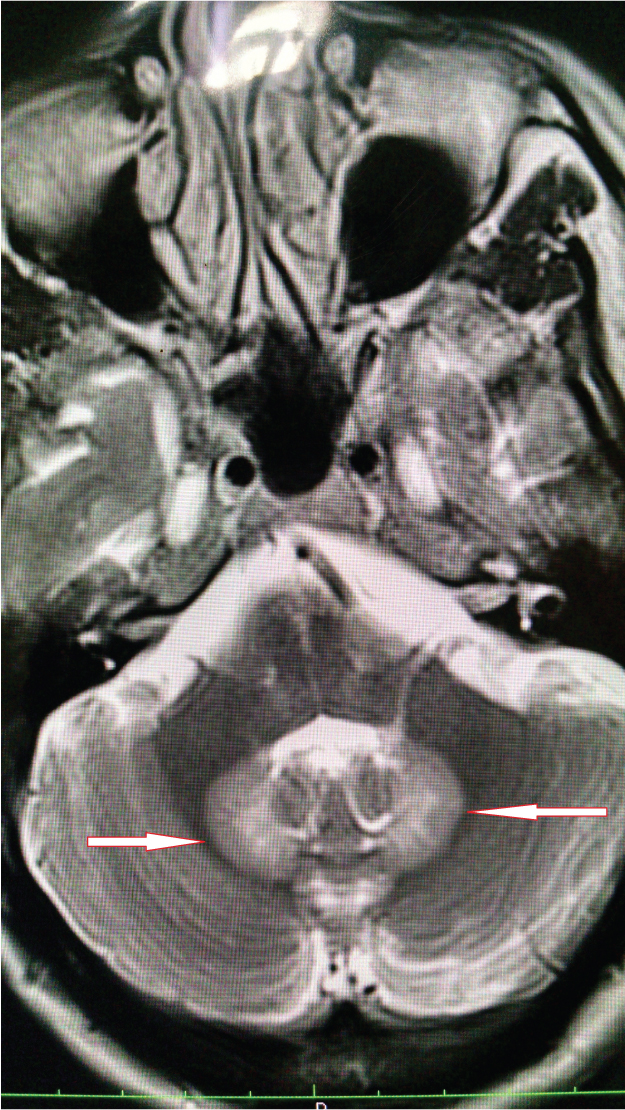

A 45-year-old male patient presented with sudden onset of vertigo, ataxia and slurring of speech since 2 days. The patient was a known case of liver abscess and was treated with percutaneous pigtail catheter drainage elsewhere and oral as well as parenteral antibiotics and was discharged after improvement in symptoms. He was treated with intravenous metronidazole in a dose of 800ml intravenous three times a day for 5 days followed by 800mg orally three times a day for 3 weeks as per his discharge summary. After one month, he came to our hospital with cerebellar symptoms as described above. On examination the patient had staccato speech, restriction of lateral gaze of both eyes and positive cerebellar signs like dysdiadochokinesia and positive Romberg’s sign. The patient was referred to Radiology department for MRI brain which showed symmetrical hyperintensities in bilateral dentate nuclei and tectum on T2W & FLAIR sequences [Table/Fig-1,2, and 3].

T2W axial image showing hyperintensity in bilateral dentate nuclei

FLAIR axial image showing hyperintensity in bilateral dentate nuclei